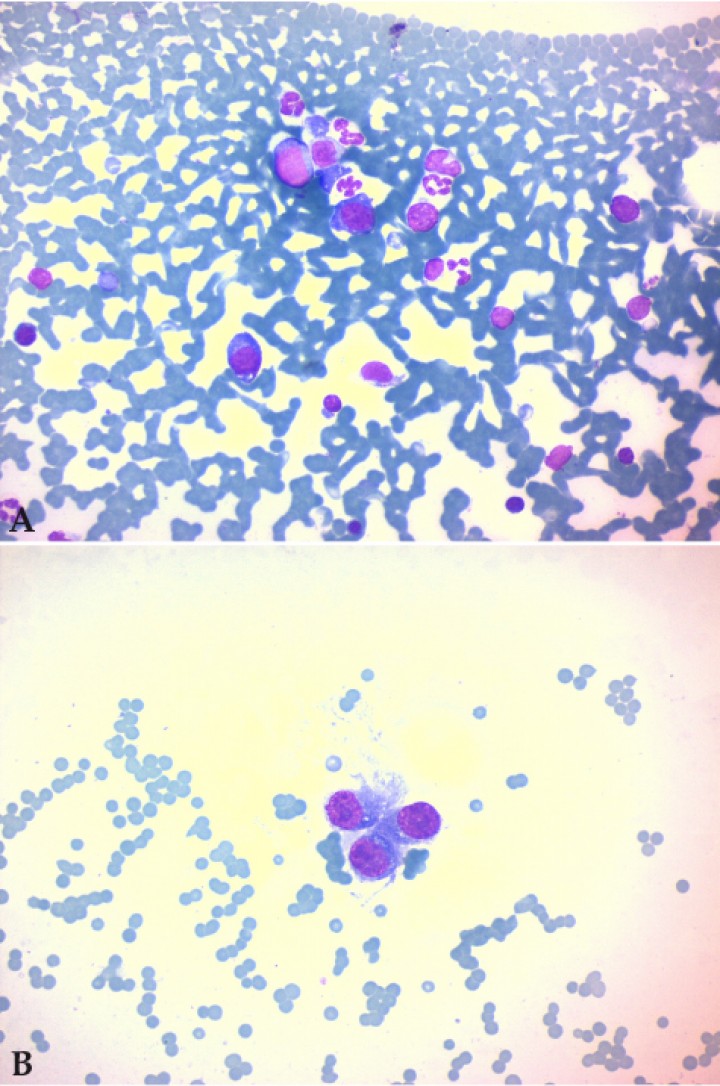

Ante estos resultados se realizaron pruebas adicionales consistentes en electroforesis de orina, estudio de proteinuria de Bence Jones mediante nefelometría, determinación de inmunoglobulinas (Ig) séricas por inmunodifusión, aspiración y citología de médula ósea (fémur izquierdo) y biopsia escisional de la masa glútea. Los resultados mostraron un pico en la fracción beta en la electroforesis (Fig. 1B), proteinuria de Bence Jones positiva para cadenas ligeras lambda (195 mg/dL), aumento marcado de IgG (8600 mg/dL, ref: 600-3800) y disminución de IgA (7,80 mg/dL, ref: 35-600) e IgM (11,70 mg/dL, ref: 70-360) séricas (Tabla 3). Los frotis de médula ósea (Fig. 2) contenían una población hematopoyética de predominio mieloide, con formas proreticulocíticas y reticulocíticas escasas, elementos megacarioblásticos ocasionales y depleción de neutrófilos maduros. Se observó la presencia relativamente abundante (superior al 10%) de elementos celulares de mediano tamaño, de citoplasma escaso a moderadamente abundante y núcleo redondo irregular, en muchos casos con nucléolo prominente. El diagnóstico fue de hipoplasia eritroide con infiltración de células redondas compatibles con células plasmáticas neoplásicas. El diagnóstico de la masa glútea fue de fibrosarcoma.

<p>Punción de médula ósea. (<strong>A</strong>) Se observan dos células plasmacitoides atípicas en el centro de la imagen, de citoplasma basófilo con leve halo claro perinuclear. (<strong>B</strong>) Elementos celulares atípicos de morfología ambigua. La textura de la cromatina y la morfología nuclear señalan compatibilidad con fenotipo plasmacítico (x400, tinción H/E).</p>

Figura 2

Punción de médula ósea. (A) Se observan dos células plasmacitoides atípicas en el centro de la imagen, de citoplasma basófilo con leve halo claro perinuclear. (B) Elementos celulares atípicos de morfología ambigua. La textura de la cromatina y la morfología nuclear señalan compatibilidad con fenotipo plasmacítico (x400, tinción H/E).

El estudio de médula ósea muestra como signo característico la presencia de plasmacitosis superior al 10% apareciendo en ocasiones, como en el presente caso, depleción de progenitores eritroides cuyo efecto será el de anemia no regenerativa. En gatos con MM, un elevado porcentaje de células plasmáticas son inmaduras y presentan marcada atipia, y un cuarto de la población celular, aproximadamente, muestra figuras en llama.[ Withrow SJ, Vail DM. Withrow & MacEwen’s Small Animal Clinical Oncology. 4th Edition. St Louis: Elsevier Saunders; 2006. ]